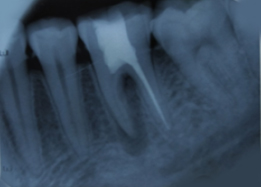

Radiograph with Prosthesis (8 Months)